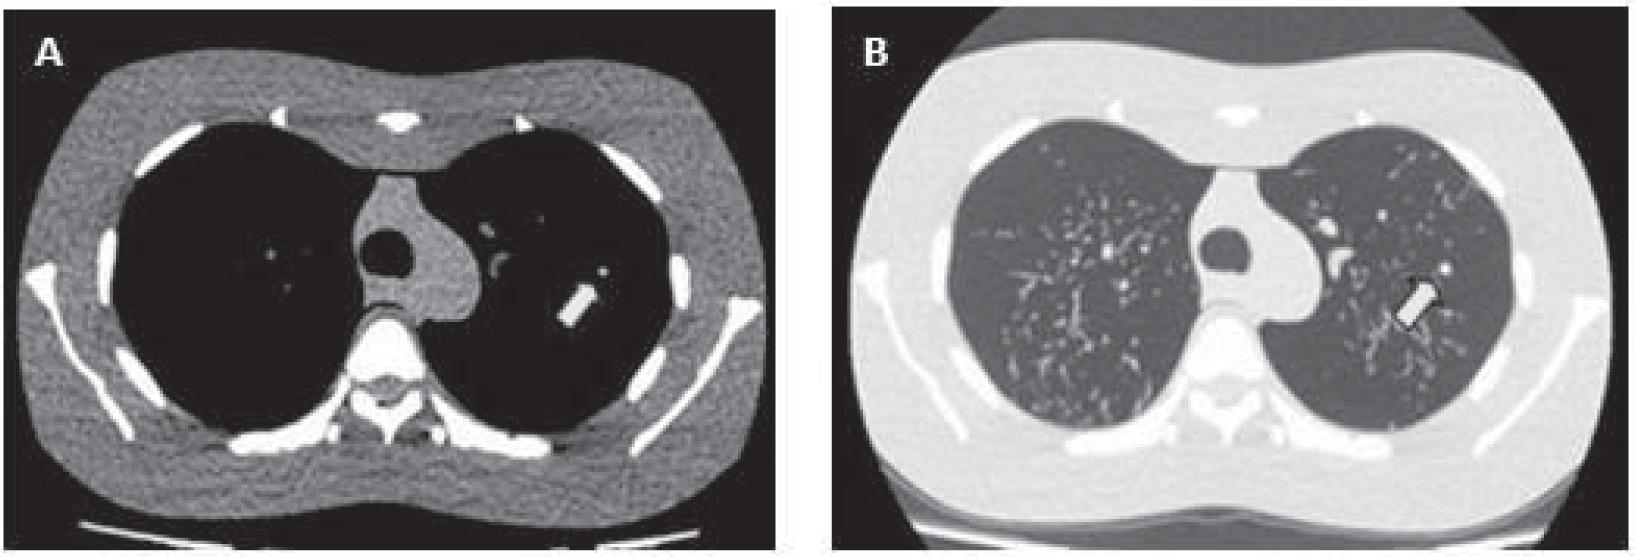

Figure 4 demonstrates an example of cross-sectional thoracic slice of CT chest acquired by the optimal protocol at target SD of 20, pitch 0.813 and 120 kVp. The CT images are displayed by window level/width (WL/WW) setting of 60/360 HU for soft tissue window (Figure 4A), and window level/width of –600/1600 HU for lung window (Figure 4B) with 5 mm simulated nodule at the 1/3 in peripheral of left lower lobe. Following the consideration for selecting the optimal protocol in our study indicated that this low-dose protocol provided an acceptable image quality of %CNR of 62% with the image scoring of 4 evaluated by 2 radiologists for nodule detection capability 5 mm, and provided the lowest radiation dose compared with other scanning protocols.

Figure 4

Computed tomography chest images with 5 mm nodule in diameter (arrow) at target SD 20, 10–400 mA, pitch 0.813 and 120 kVp, and displayed with (A) soft tissue window, WL/WW setting of 60/360 Hounsfield Units (HU) and (B) lung window, WL/WW setting of –600/1600 HU